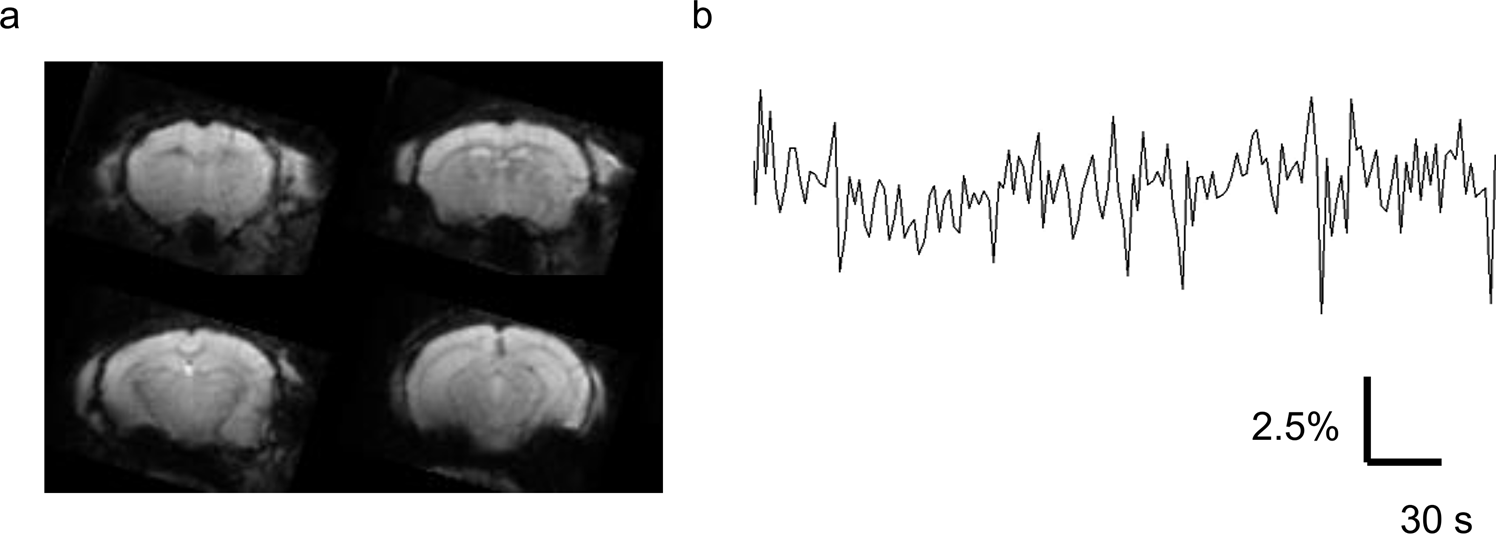

Figure 2

From: The impact of fasting on resting state brain networks in mice

(a) Multiple slices of unprocessed functional images of a representative mouse. (b) Representative spontaneous fluctuation of BOLD signals in the left retrosplenial cortex. Vertical axis, percent change of BOLD signals.